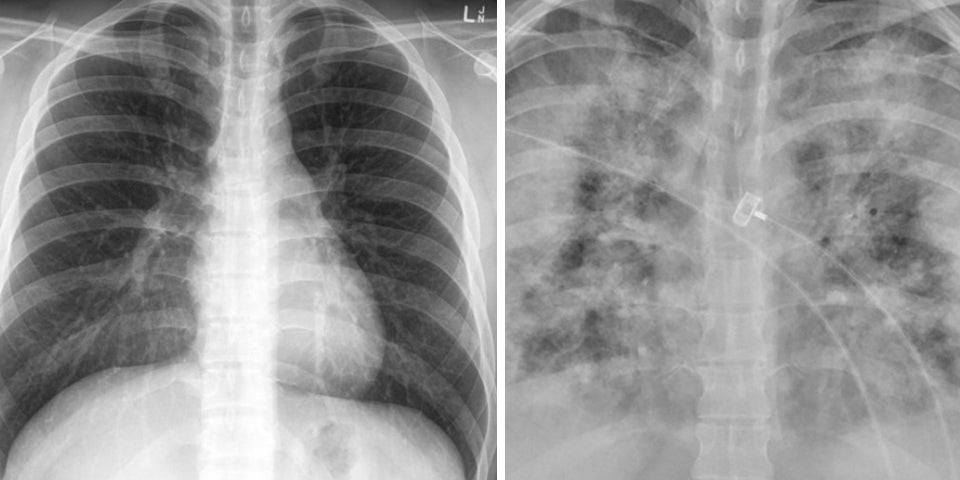

Wie groß der Unterschied punkto Lungenschäden zwischen Corona-Geimpften und Ungeimpften sein kann, zeigen zwei Röntgenbilder.

Wie groß der Unterschied punkto Lungenschäden zwischen Geimpften und Ungeimpften sein kann, zeigen zwei Röntgenbilder:

With Without

Vaccination Vaccination pic.twitter.com/GIcb5mJQz9

Auf den Röntgenaufnahmen, die Faheem Younus, Leiter der Abteilung "Infectious Diseases" an der University of Maryland, auf Twitter geteilt hat, sieht man zwei Lungen, die sich deutlich unterscheiden. In beiden Fällen stammen die Bilder von einem Covid-19-Patienten. Auf der einen Aufnahme sind deutlich mehr helle Schatten zu sehen als auf der anderen. Das Röntgenbild zeigt die Lunge einer ungeimpften Person. Bei den weissen Schatten handelt es sich um sogenannte Milchglastrübungen, welche entstehen bei Entzündungen der Lunge.